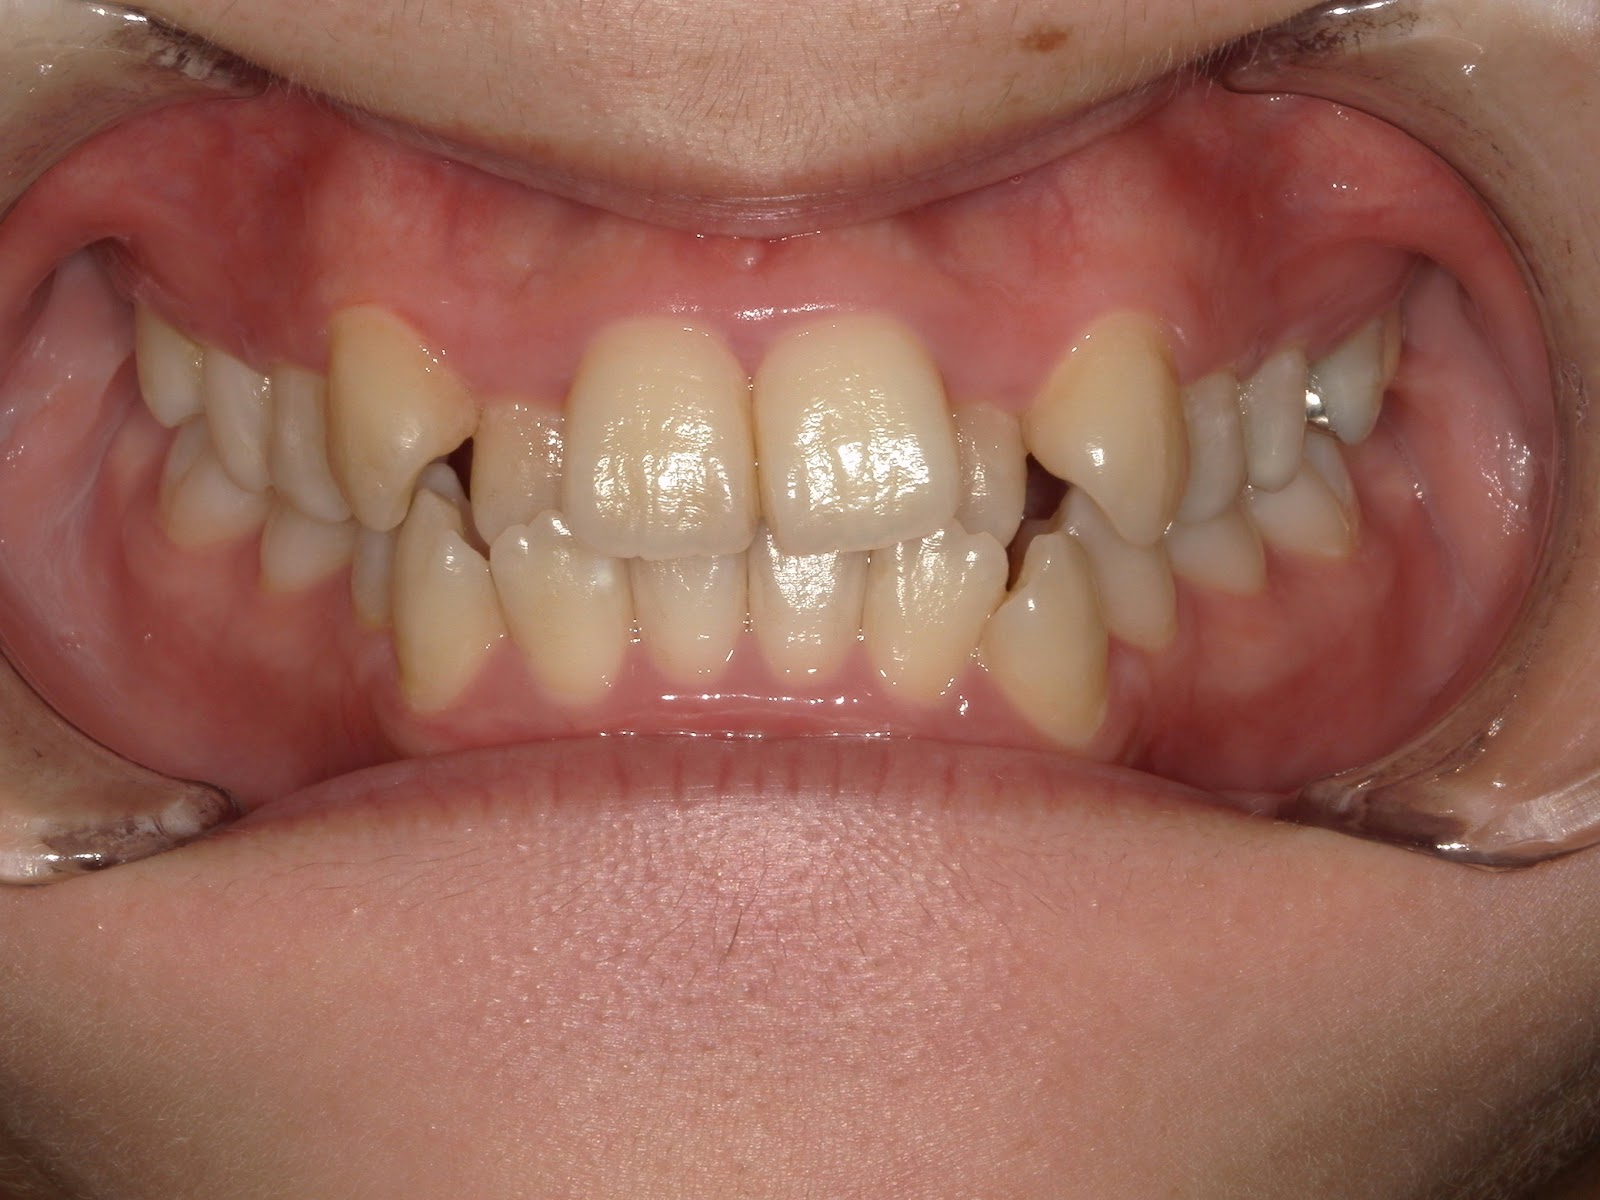

叢生歯列 治療例

治療前

| 患者様 | 女性 21歳 |

|---|---|

| 主訴 | 歯並びがガチャガチャしているので治したい |

| 診断 | 叢生歯列不正咬合 |

| 治療方針 | 上顎右側第一小臼歯、上顎左側第二小臼歯(第二小臼歯が根管治療歯のため当該歯を抜歯) |

| 治療に使用した装置 | マルチブラケット(セルフライゲーションブラケット) アンカースクリュー×1 |

| 治療期間 | 1年6カ月 |

| 治療回数 | 18回 |

| 治療費(自費診療) | 矯正治療費総額824,000円(税込み) |